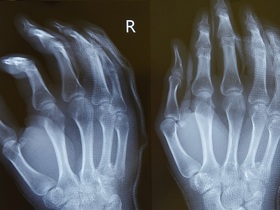

Кисть человека — чрезвычайно деликатный орган со сложной структурой, который в повседневной жизни испытывает большие функциональные нагрузки. Суставы, кости, мышцы, связки, сухожилия, нервы и сосуды кисти часто травмируются или страдают от заболеваний. Консервативное лечение помогает не всегда, а оперативное требует особого подхода.

Только осмотра на первичном приеме мало, чтобы точно установить диагноз. Необходимо пройти дополнительные обследования, которые визуализируют повреждение, помогут определить его степень и зону распространения на соседние ткани.

Во время хирургического вмешательства кисть пациента размещена под микроскопом. Восстановление сухожилий, сосудов и нервов происходит с помощью микроинструментов. В клинике МЕДИКОМ также проводят хирургические операции кисти под рентгенологическим или УЗИ контролем.